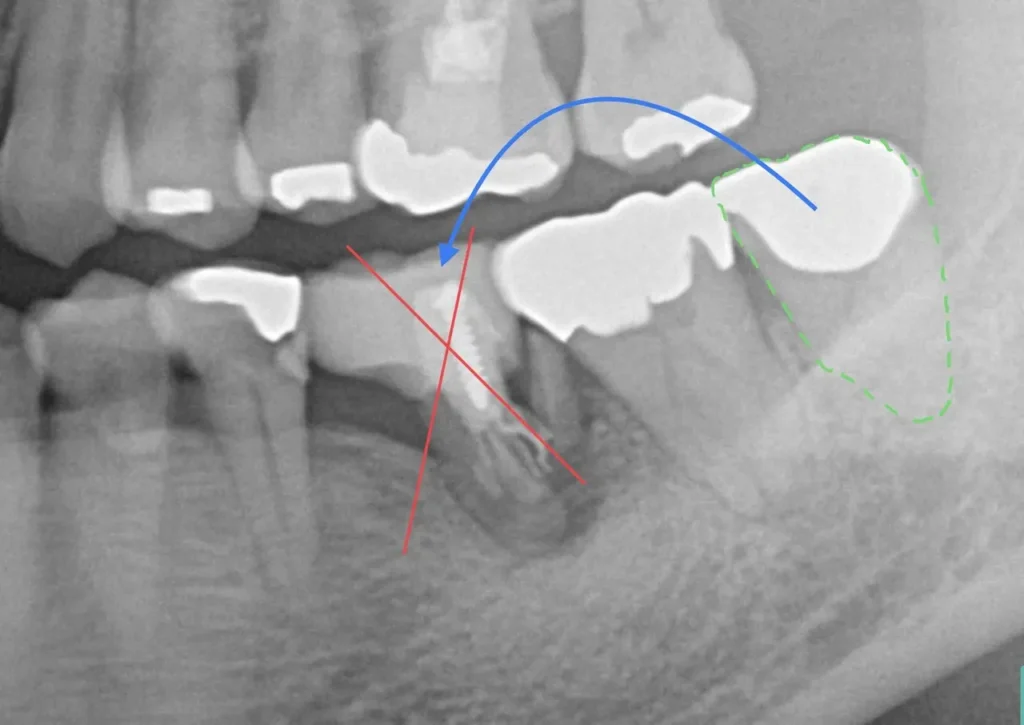

左下の奥歯が根が割れて保存不可能です。奥の咬合わせの余っている親知らずを移すことににしました。移植した歯は、根管治療とクラウン修復が必要です。

奥3番目の歯の根が割れています。

長年の放置で土手の骨が吸収。